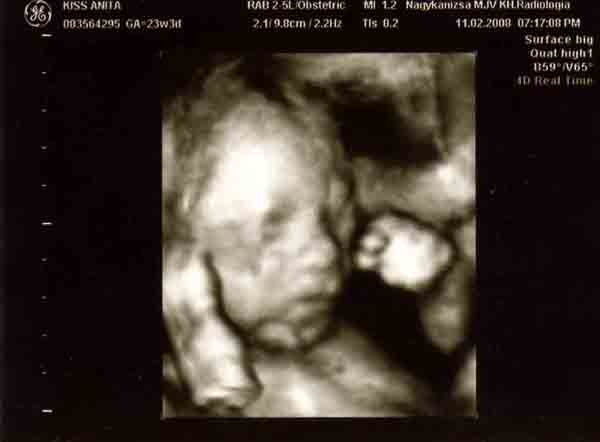

Banika: nagyon jok lettek a kepek!!! Olyan szepek!